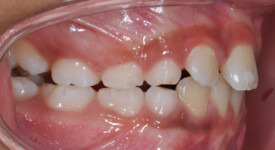

Before Transformation!